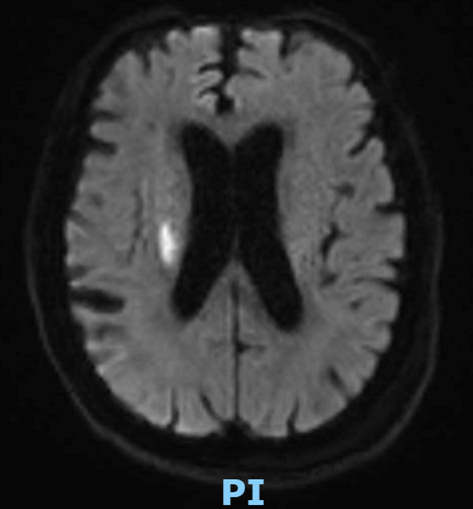

Le type d’hémianopsie est très important car il permet de localiser une atteinte neurologique, en connaissant le trajet des voies optiques.

Figure d’après le Collège des enseignants de neurologie (CEN). Altération aiguë de la vision.

Cette question supposait d’avoir bien en tête le schéma des voies optiques, et d’avoir des repères sur les principaux territoires vasculaires cérébraux et l’atteinte clinique associée. Il bien mentionné par le CEN que l’hémianopsie latérale homonyme gauche peut se voir dans un AVC sylvien superficiel droit.